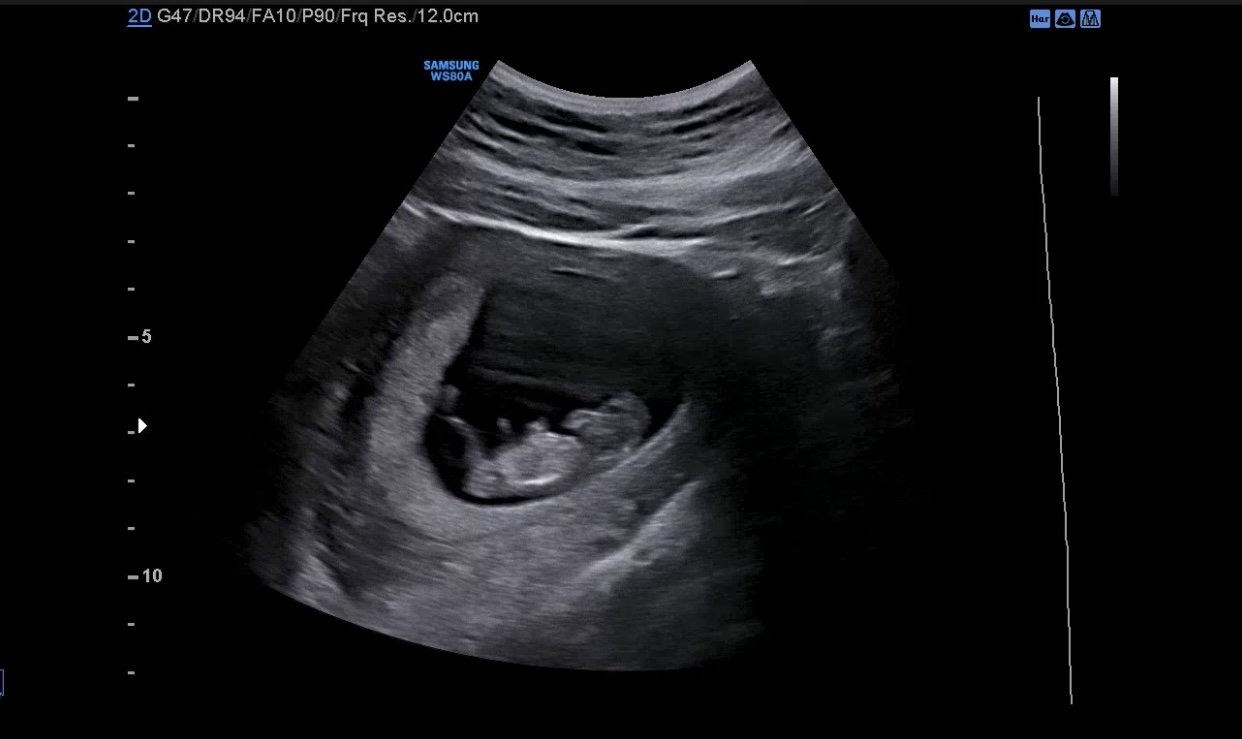

10주차 예비아빠입니다!

아직도 실감이 안나고 어색하지만

아내 케어 잘하고 준비 열심히해서

좋은 아빠가 되겠습니다!

응원 부탁드립니다